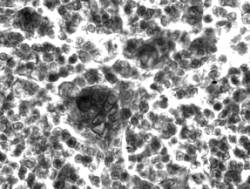

Срезы окрашивали железным гематоксилином по Рего и Маллори. Результаты. Контроль-1. У животных

до операции количество мозгового вещества в тимусе составляло 15.48±1.10%.

Тимоциты располагались плотно. МИ и

количество лимфоидных клеток с пикнотическими

ядрами равнялось 7.37±1.12‰ и 0.48±0.04 % соответственно. На единицу площади

мозгового вещества приходилось 0.5 телец Гассаля. Они имели разную величину и находились на разных стадиях

развития. Преобладали тельца, в центре

которых отмечались тени клеток с гипертрофированными ядрами или формировалась

пустая полость (рис.1). В опыте-1 через